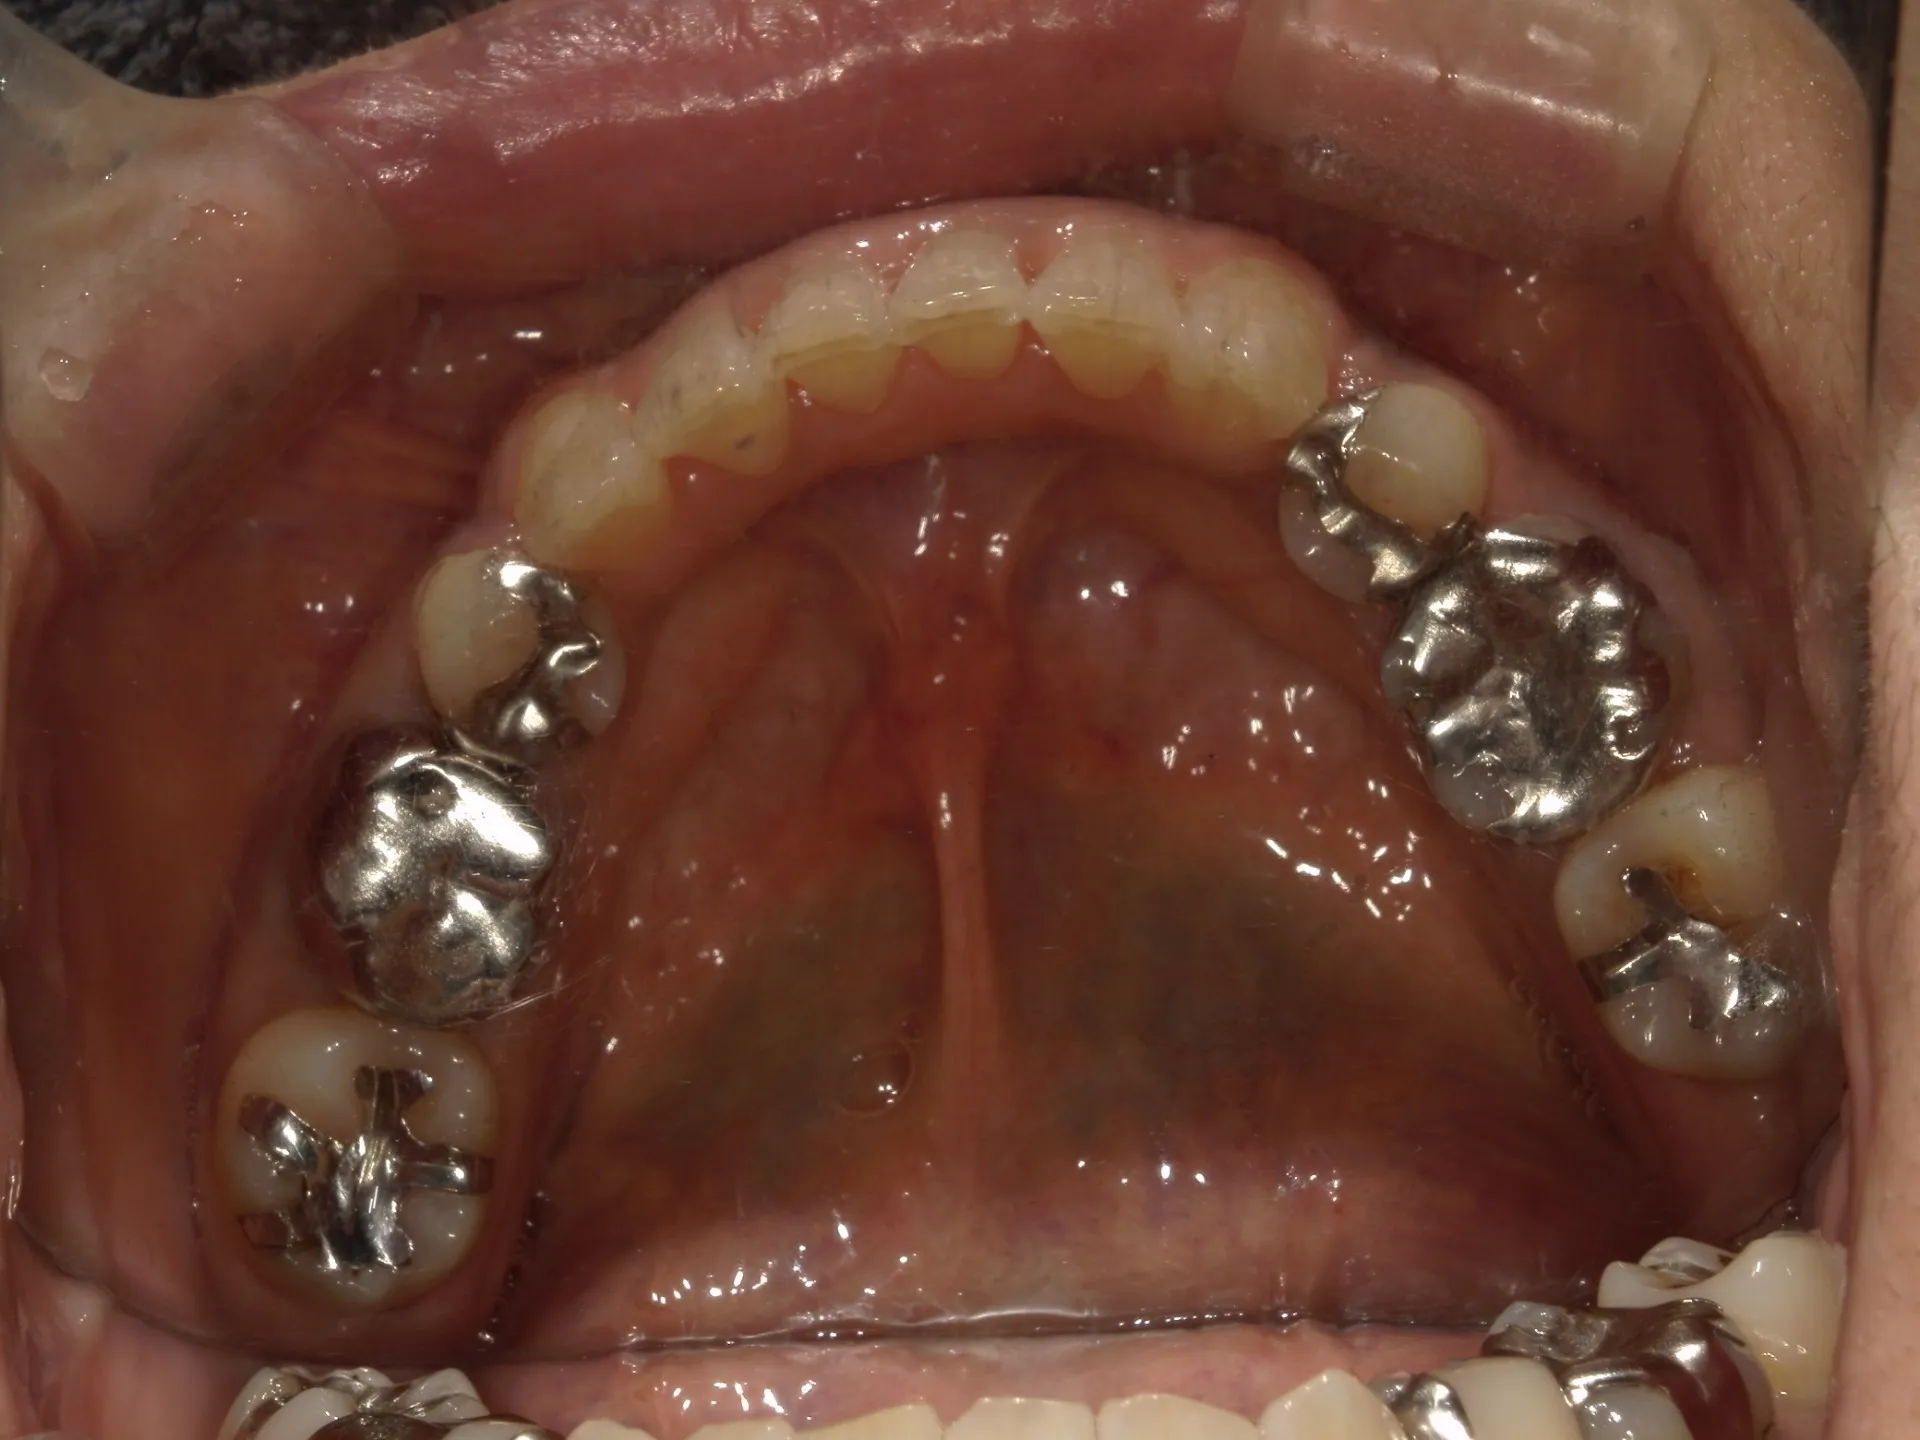

今回は65歳以上でも矯正治療を開始した症例についてご紹介いたします。

しかし、年齢がたとえ定年を迎えたあとであっても十分に矯正が行えて、今後の歯磨きが容易になり、虫歯や歯周病のリスクが減らせて歯を残すことが出来たり、歯並びが良くなったことでモチベーションも上がるなどの矯正後のメリットも非常に高いため、健康的な生活を行う上でも矯正治療は行うことをお勧めします。